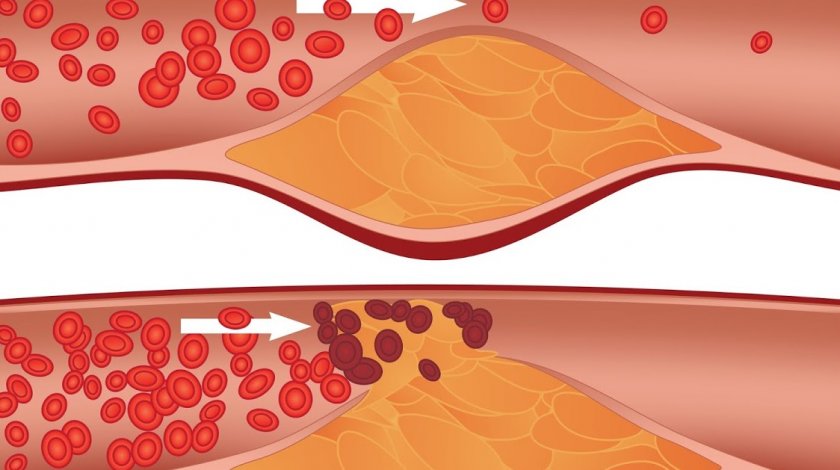

При атеросклерозе поражаются артерии. В их стенках откладываются жировые масла, что приводит к утолщению и деформации сосудов и нарушению их функций. Атеросклероз является многофакторным процессом. Определенную роль в развитии атеросклероза играет холестерин. В связи с чем обильное питание с большим количеством жиров и углеводов, гиподинамия, нарушение витаминного баланса, курение, употребление алкоголя не способствуют профилактике заболевания.

Проявления атеросклероза зависят от степени сужения пораженного сосуда и его локализации (аорта, мозговые сосуды, сосуды брюшной полости).

В вине содержатся полифенолы — антоцианы (красные красящие вещества), флавонолы (желтые красящие вещества), флаволы, катехины, танины и др. Большое содержание в вине полифенолов облегчает циркуляцию крови как по крупным сосудам, так и по мелким (микроциркуляцию). При этом улучшаются реологические (вязкоэластичные) свойства крови, что имеет существенное значение, так как нарушение этих свойств является причиной таких заболеваний, как атеросклероз, гипертония, инсульт и инфаркт. Количество вина на прием не должно превышать 50 мл. Курс винолечения (энотерапии) составляет 2—3 недели.

При атеросклерозе поражаются артерии. В их стенках откладываются жировые масла, что приводит к утолщению и деформации сосудов и нарушению их функций. Атеросклероз является многофакторным процессом. Определенную роль в развитии атеросклероза играет холестерин. В связи с чем обильное питание с большим количеством жиров и углеводов, гиподинамия, нарушение витаминного баланса, курение, употребление алкоголя не способствуют профилактике заболевания.

Проявления атеросклероза зависят от степени сужения пораженного сосуда и его локализации (аорта, мозговые сосуды, сосуды брюшной полости).

В вине содержатся полифенолы — антоцианы (красные красящие вещества), флавонолы (желтые красящие вещества), флаволы, катехины, танины и др. Большое содержание в вине полифенолов облегчает циркуляцию крови как по крупным сосудам, так и по мелким (микроциркуляцию). При этом улучшаются реологические (вязкоэластичные) свойства крови, что имеет существенное значение, так как нарушение этих свойств является причиной таких заболеваний, как атеросклероз, гипертония, инсульт и инфаркт. Количество вина на прием не должно превышать 50 мл. Курс винолечения (энотерапии) составляет 2—3 недели.